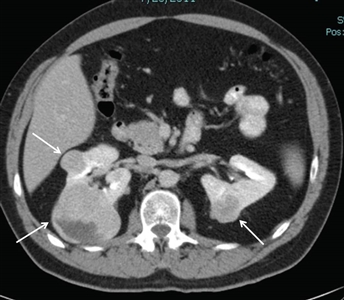

Approximately 25% to 35% of individuals with BHD develop renal tumors,[1,4,10,11] which are multifocal in 65% of cases and often bilateral. The frequency of renal tumors among patients with BHD whose medical records were reviewed was 20%, and the frequency of renal tumors among BHD patients evaluated by CT scan was 29%. Most renal tumors associated with BHD are slow growing. Median age at diagnosis is 48 to 50 years (range, 31–71 y).[2,12,13,14] Men developed renal tumors more often than did women (27 males; 11 females). Renal tumors associated with BHD seem to occur at a younger age than do sporadic forms of renal cell cancer (RCC), in which the median age at diagnosis is 64 years.[15]Figure 1 depicts bilateral renal tumors in a patient with BHD.

Figure 1. Birt-Hogg-Dubé syndrome–associated renal tumors are commonly multifocal and bilateral. Arrows indicate the locations of the tumors.